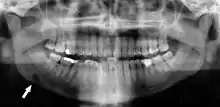

Atherosclerosis is attributed to risk factors that include cigarette smoking, hyperlipidemia, obesity, diabetes mellitus, and hypertension (high blood pressure). These factors, however, do not fully account for the risk of disease. Atherosclerosis has been conceptualized as a chronic inflammatory response to endothelial cell injury[24] and dysfunction possibly arising from chronic dental infection. In 2010, using the previously validated Mattila panoramic radiographic index to quantify the totality of dental infection (i.e., periapical and furcal lesions, pericoronitis sites, carious tooth roots, teeth with pulpal caries, and vertical bony defects), Friedlander’s group determined that individuals with carotid artery atheromas on their panoramic radiographs had significantly greater amounts of dental infection/inflammation than atherogenic risk-matched controls devoid of radiographic atheromas.[25][26] While the Mattila index had been previously used to relate the extent of dental infection to coronary artery disease, this research is the first to link the full range of dental disease that it measures to panoramic radiographs evidencing calcified carotid artery atherosclerosis.